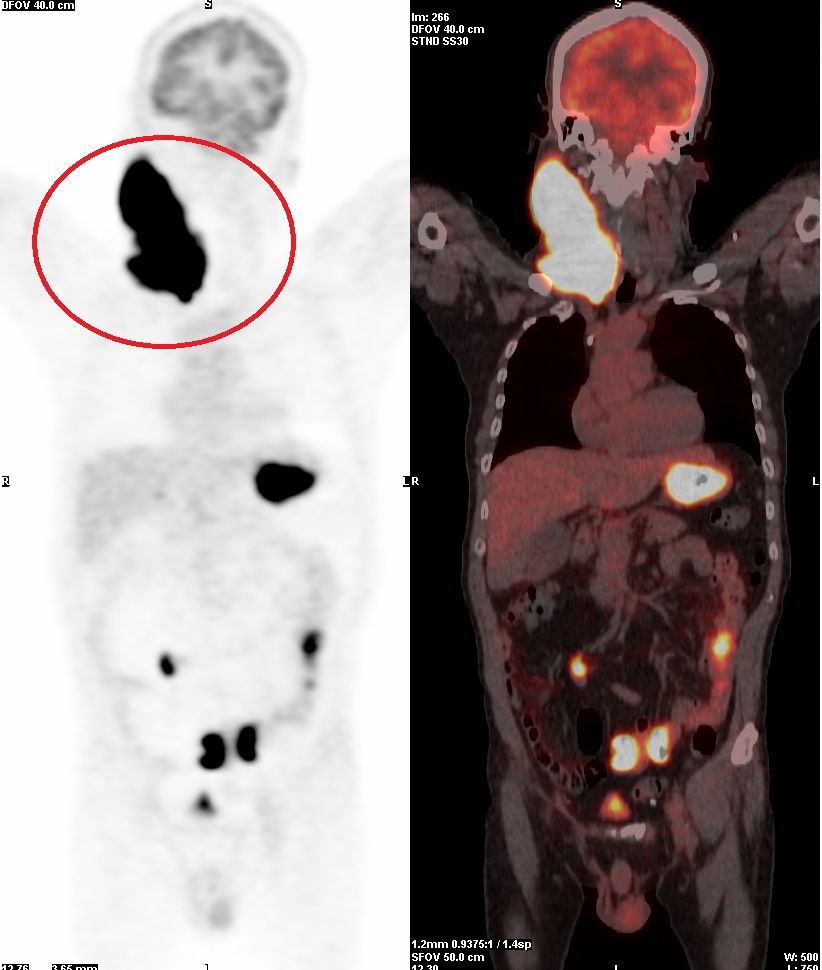

斷層掃描檢查發現,患者頸部的腫瘤與氣管僅僅相隔0.1公分,幾乎已經壓迫到呼吸道,若是再晚一步,可能會因窒息而喪命,加上治療前,患者已經出現自發性的「腫瘤溶解症候群」,這常見於化療過程中腫瘤細胞大量死亡後,細胞內代謝廢物釋出至血液中,進而阻塞腎小管,造成高尿酸血症、高鉀血症,也大幅增加急性腎衰竭與需要洗腎的風險。

▲斷層掃描檢查發現,患者頸部的腫瘤與氣管僅僅相隔0.1公分,幾乎壓迫呼吸道。